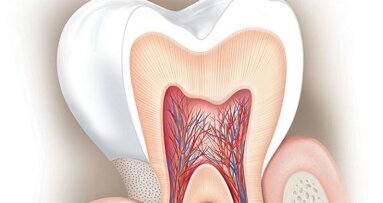

SEATTLE, US: Existing treatments for dentine hypersensitivity, including desensitisers and dentinal tubule blockers, offer only temporary relief for patients. A permanent solution would be one that provides lasting occlusion of the exposed dentinal tubules and mineralisation of the peritubular dentine. A team of researchers from the University of Washington in Seattle has developed a means of achieving just that. Their solution has shown promising results and can be used in various oral care applications.

To address the issue of dentine hypersensitivity, the researchers used a specifically tailored amelogenin-derived peptide which binds to calcium and phosphate ions, foundational components of tooth mineral, to construct new mineral micro-layers on the exposed dentine. This process was designed to be biomimetic, resembling the process by means of which teeth are developed in the body.

When testing the mineral layers, the researchers observed that the peptide bonded well to the dentine surface by attracting calcium and phosphate ions, forming a hydroxyapatite mineral layer. The resulting layer not only occluded the dentinal tubules but also promoted dentine repair by remineralising the surface, resulting in a well-integrated and long-lasting layer.

Furthermore, the mineral layer displayed notable hardness, and the researchers suggested that the layers are capable of enduring the mechanical and thermal stresses typical of the oral environment.